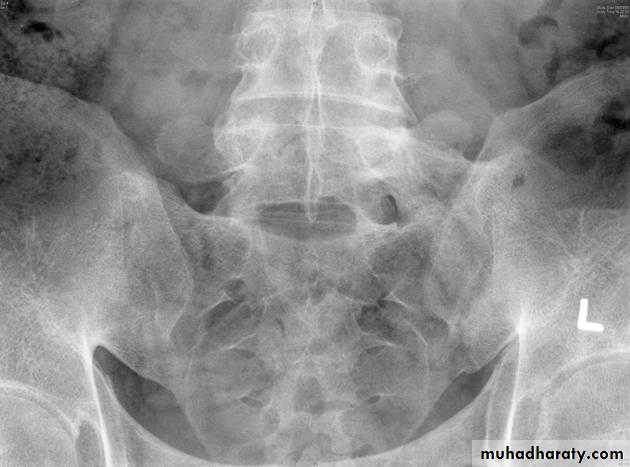

ANKYLOSING SPONDYLITIS (AS)

• Seronegative spondyloarthropathy of the axial skeleton and proximal large joints.• Clinical: males >> females. HLA-B27 in 95%. Insiduous onset of back pain and stiffness. Onset: 20 years.

• Radiographic features

• * SI joint is the initial site of involvement:

• bilateral, symmetrical

• Erosions: early ,Sclerosis: intermediate , ankylosis: late

• * Contiguous thoracolumbar involvement

• Vertebral body "squaring": early osteitis

• * Syndesmophytes

• * Bamboo spine: late fusion and Bamboo spine

• ligamentous ossification

• *ankylosed spine (fracture)

• * Enthesopathy is common(("whiskering of tuberosities )

• * Arthritis of proximal joints (hip > shoulder) in 50% ,erosions and osteophytes